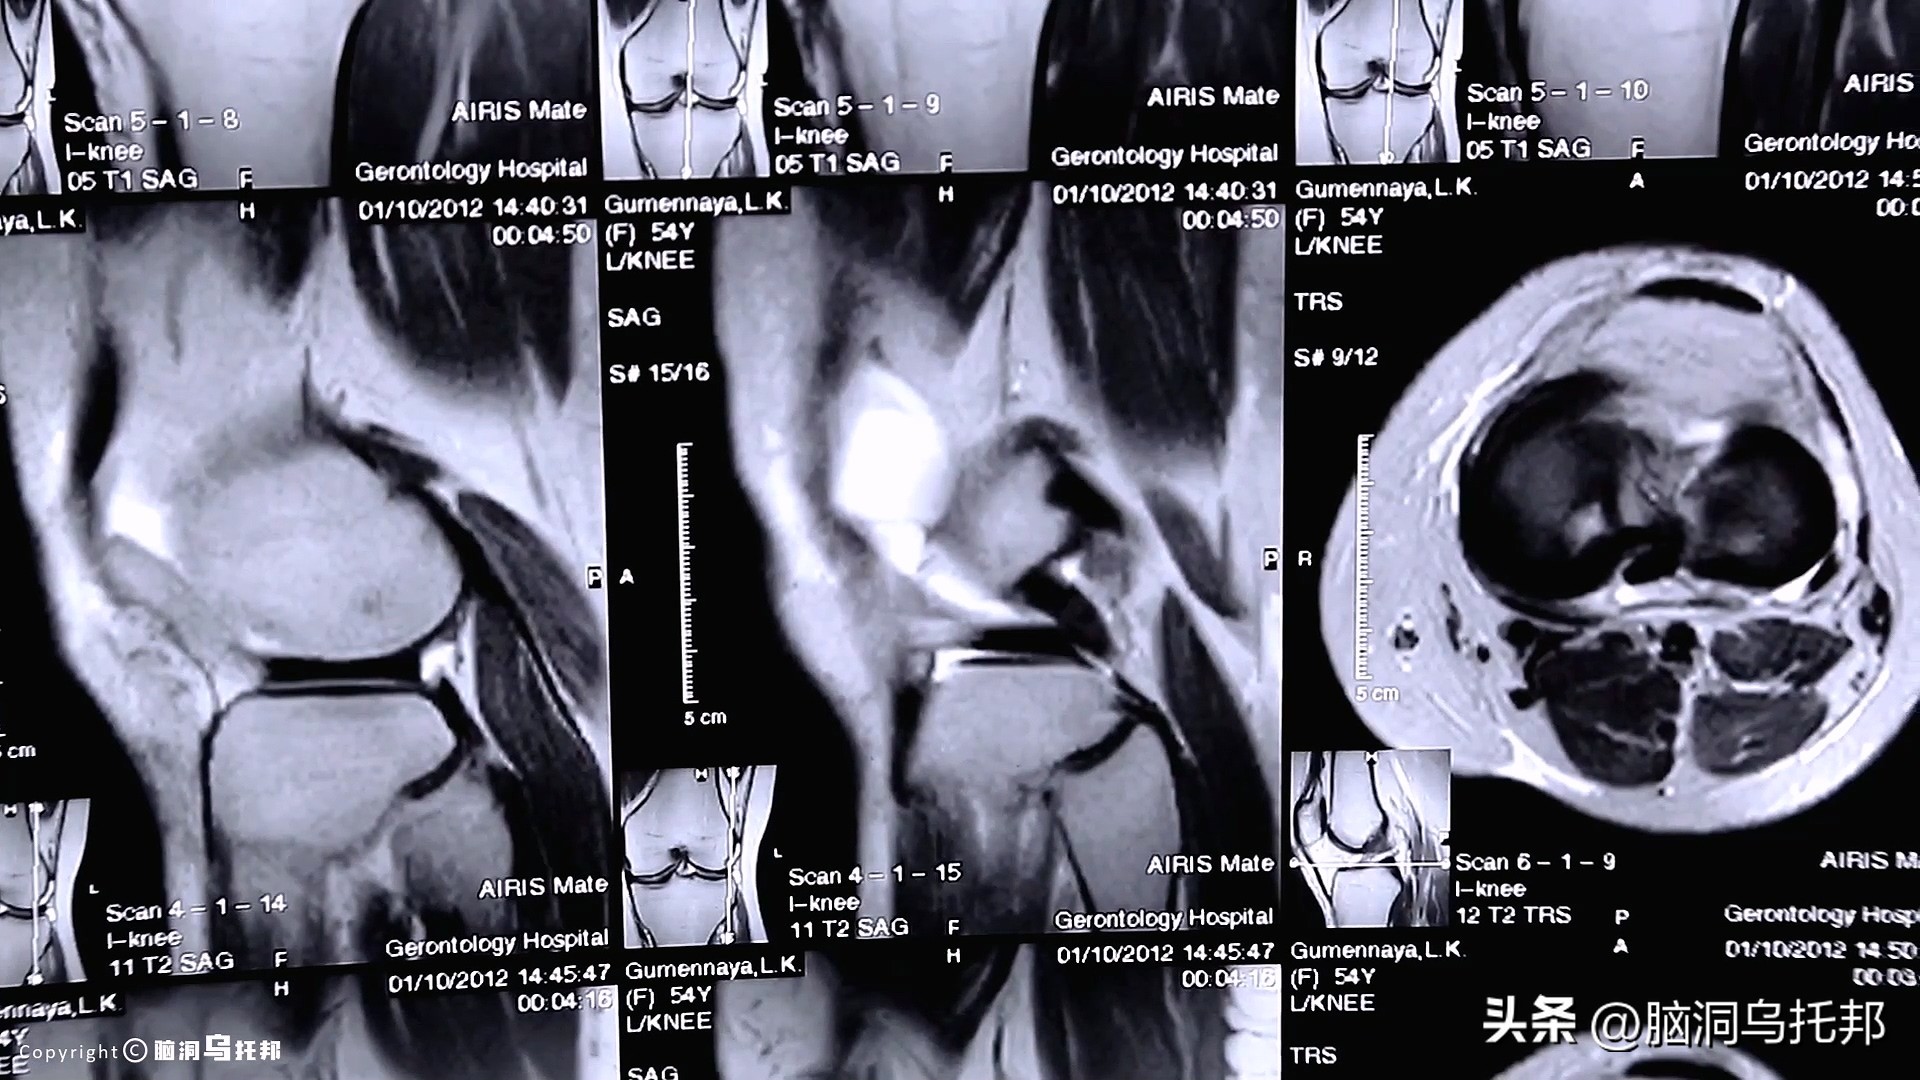

屋漏偏逢连夜雨,2016年,舟舟在北京查出肺癌。

影像检查结果显示,主动脉上有一个恶性肿瘤,鸡蛋大小。